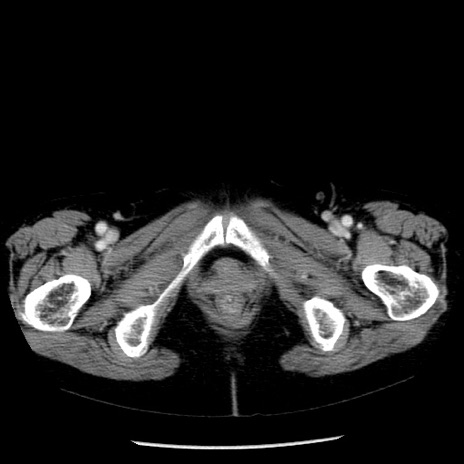

冠状断像

【症例】70歳代女性

【主訴】腹痛、嘔吐

【現病歴】15時間程前(昨晩)より腹痛あり。今朝になっても症状の改善なく、嘔吐あり。腹痛も増悪あり、救急外来受診。

【既往歴】子宮癌全摘術後

【身体所見】意識清明、BP 121/72mmHg、P 74bpm、SpO2 100%(RA)、腹部:平坦・軟、腸雑音ほぼ聴取せず。下腹部・心窩部・臍左上に圧痛あり。反跳痛なし。

【データ】WBC 10600、CRP 0.15